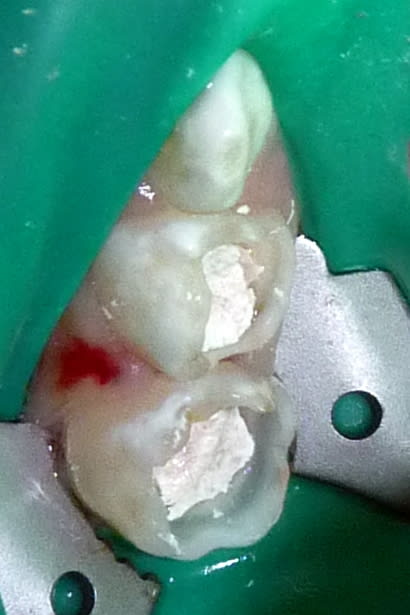

Dans le cas ci-dessous, la 1ère photo est prise après début d’éviction carieuse : sur la 4, on voit déjà la pulpe par transparence. Les tubuli dentinaires d'une dent temporaire sont beaucoup plus larges et nombreux que sur une dent permanente. Ainsi, une carie dentinaire infecte très rapidement la pulpe camérale. Faire une restauration sans pulpotomie dans ce cas aurait probablement abouti à une nécrose à moyen terme.